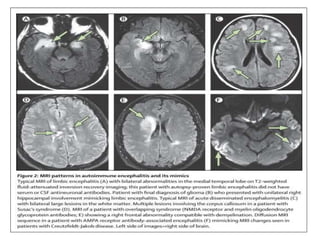

IMAGING

MRI :

• Mesial temporal hyperintensities, either unilateral or bilateral

with or without enhancement after gadolinium

administration, are classic autoimmune limbic encephalitis

findings.

• Normal imaging is common, particularly in the early illness

stages

• Extratemporal abnormalities sometimes observed.

• If lesions are not in a typical distribution or have avid

enhancement, other inflammatory (eg. neurosarcoidosis) or

oncologic (eg. lymphoma) diagnoses should be considered.

FUNCTIONAL IMAGING :

• Global hypometabolism is the most common feature

encountered in patients with autoimmune encephalopathies.

• However, focal hypometabolism can also be encountered.

• In instances where the patient has seizures, hypermetabolism

can occur.